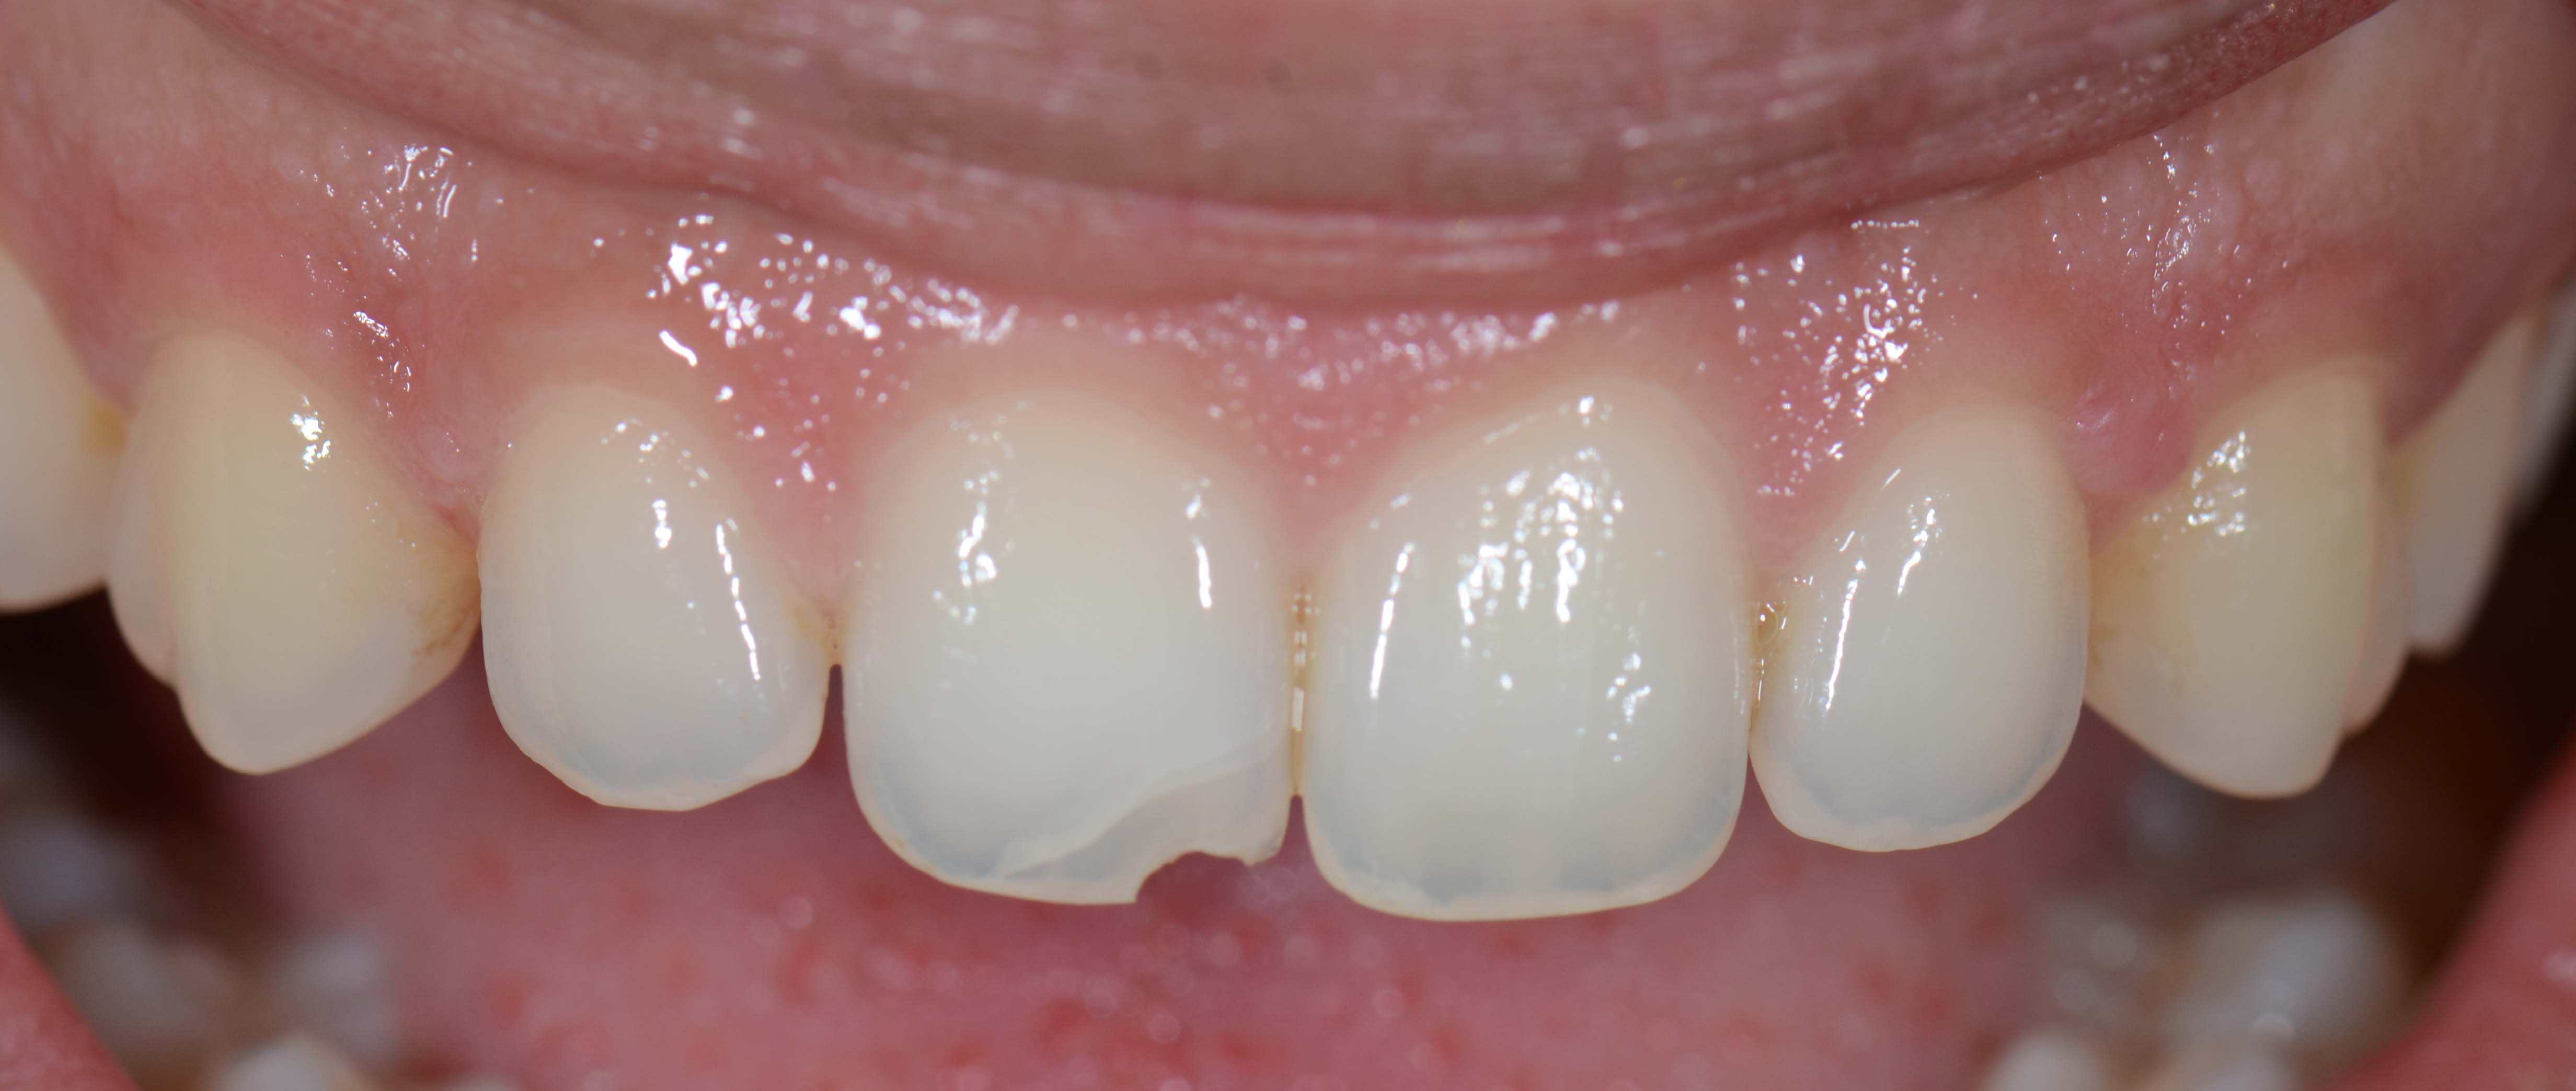

3. Fotografias

Tratamentos urgentes serão executados se necessário, como no caso à esquerda.